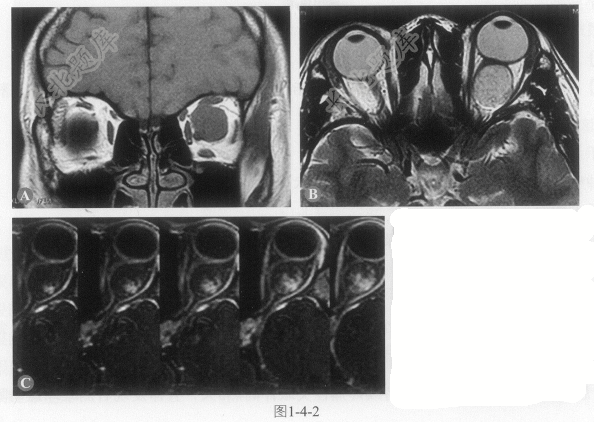

患者女性,30岁,左侧眼球突出伴运动障碍6个月。MRI示左侧眼眶肌锥内椭圆形占位。增强扫描明显强化,眼肌及眼环正常(图1-4-2,彩图1-4-2D)。

- 多项选择题1.根据此患者眼眶MRI表现,最可能的诊断是:

A、神经鞘瘤

B、炎性假瘤

C、海绵状血管瘤

D、视神经胶质瘤

E、视神经鞘脑膜瘤

- 多项选择题2.下列有关该肿瘤的描述,错误的是:

A、成年人最常见的眼眶内原发性肿瘤

B、中年女性多见

C、眼外肌明显增粗

D、多位于肌锥内

E、肿瘤内见大小不等的薄壁血管腔

- 多项选择题3.下列关于该肿瘤的影像表现,正确的是:

A、T

WI为低信号,T2WI为高信号B、渐进性强化

C、强化持续时间长

D、早期显著均匀强化

E、眼球可有受压